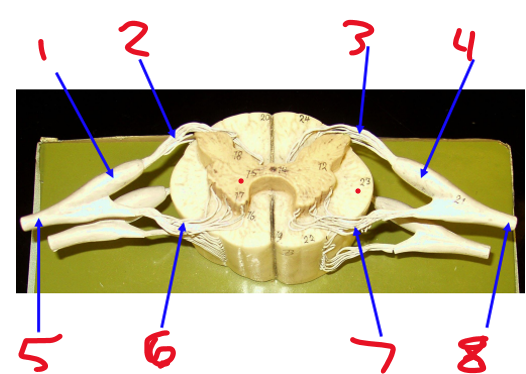

Name structure 1

Dorsal root ganglion

Name structure 2

Dorsal root

Name structure 3

Name structure 4

Name structure 5

Spinal nerve

Name structure 6

Ventral root

Name structure 7

Name structure 8